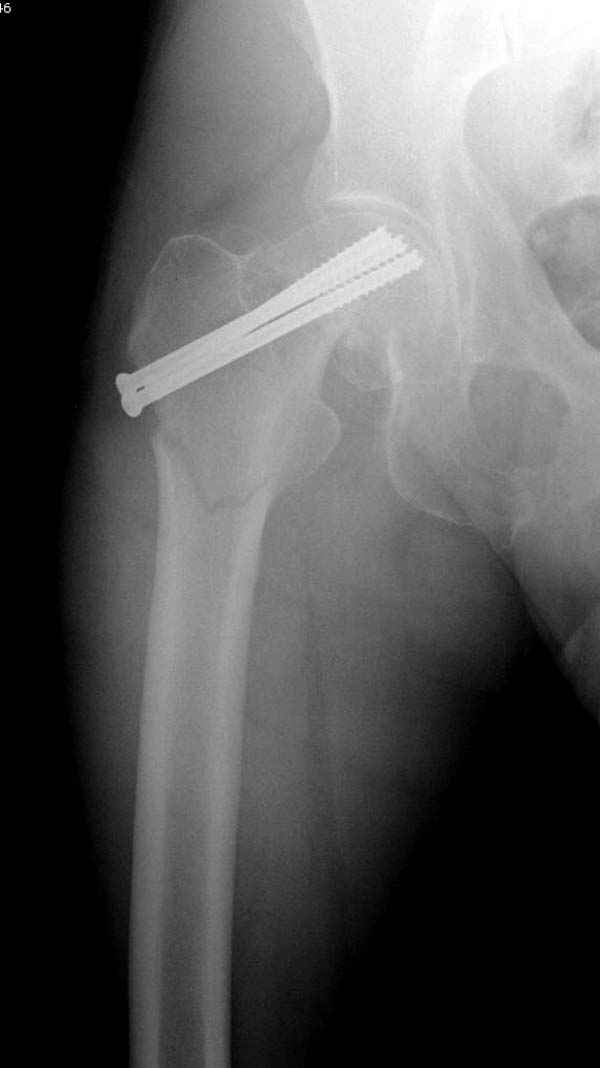

[Ortho] неполный перелом шейки

Профилактику дальнейшего раскола неполного перелома шейки провели тремя канюлированными шурупами.

На второй день после выписки упал дома. Снимки приложены. Коллеги рекомендуют удаление шурупа и вытяжение. Что делать?